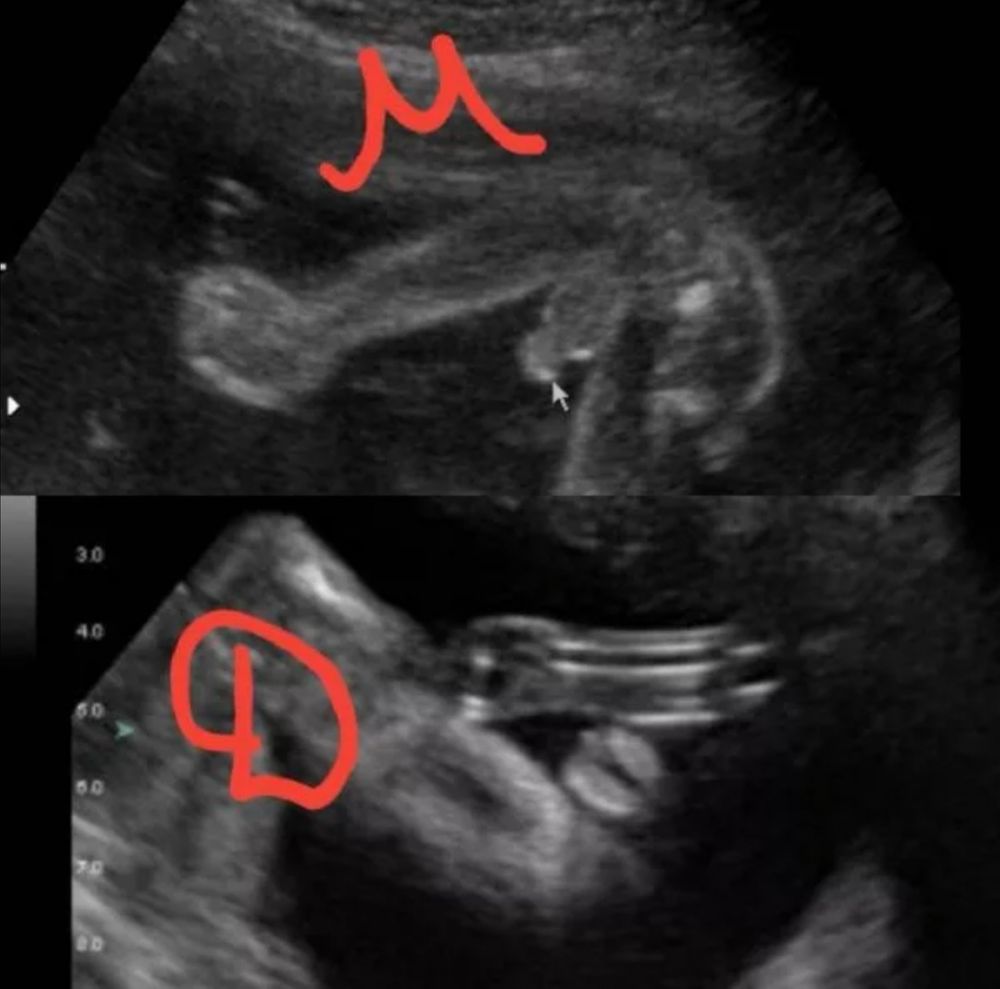

Уже добавляла такую картинку кому-то в пост)) посмотрите, может вспомните, что вы увидели. Это на сроке 20 недель (из интернета). У мальчиков уже прям виден писюн, а у девочек половые губки и клитор. П.с. а у нас в ЖК говорят пол бесплатно, если хочешь его знать, всё от врача зависит, меркантильных много очень...

Лена, у мальчика торчит просто да плюс ещё писюн, у девочки тоже выпирает бугорок

Вот снимок сыночка в 16 недель, там уже торчит так, что не заметить сложно.